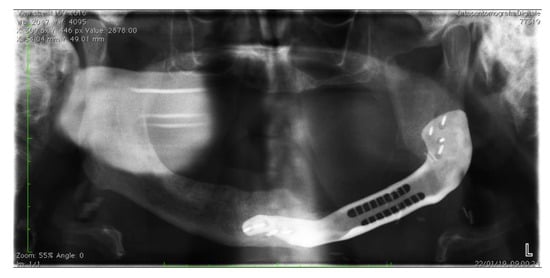

2.1. Protocol for Computer-Assisted Design and Manufacturing Bridging Plate

2.2. Surgical Procedure